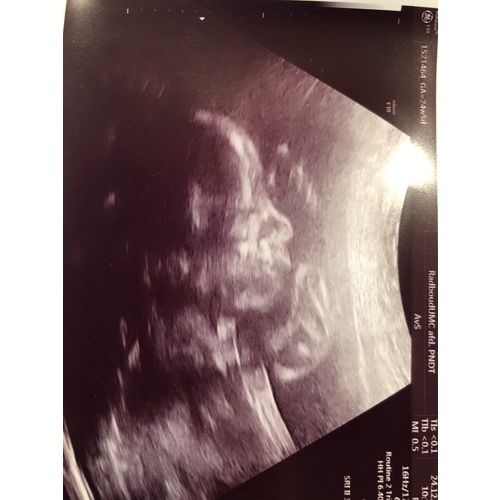

Als ik naar die afbeelding kijk... Zou je zeggen dat wij een jongetje krijgen..of niet..?

Meisjes hebben een veel rondere schedel aan de voorkant.. Mijn man heeft ook een langwerpig gezicht...

Wie wil een gokje wagen? Jongen of meisje 馃檴馃檴

Girl. En ze lijkt een beetje boos te kijken hehe

Die van ons?

Ik neig meer naar boy.. Zeg maar 75%. Had je nog een andere foto?

Nee helaas niet. Misschien woensdag weer 茅茅n.. Hij is echt niet zo mooi als al die andere foto's hier he!

Ik zou een jongetje echt leuk vinden, beide kids hopen er ook op haha. Man stiekem ook..